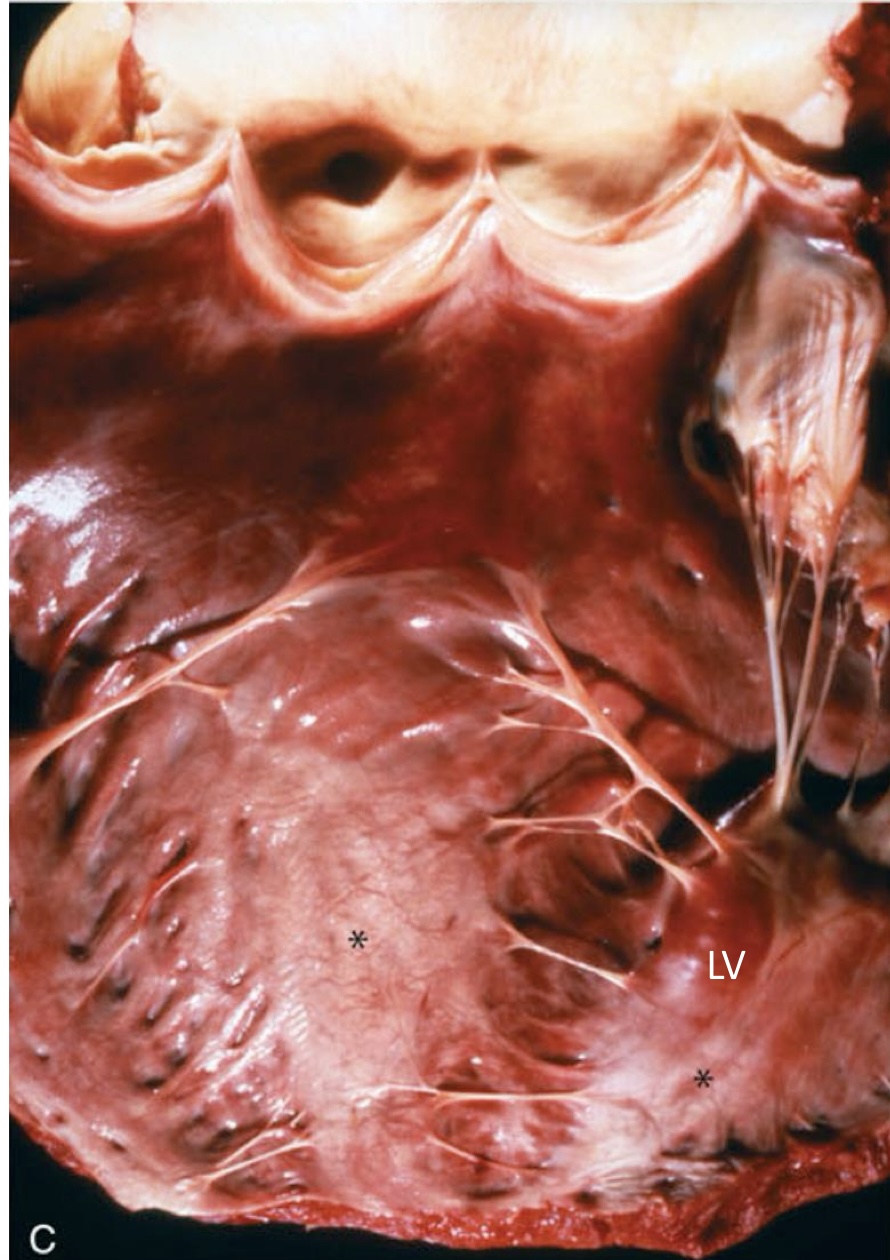

what is the asterisk showing?

endocardial mineralization